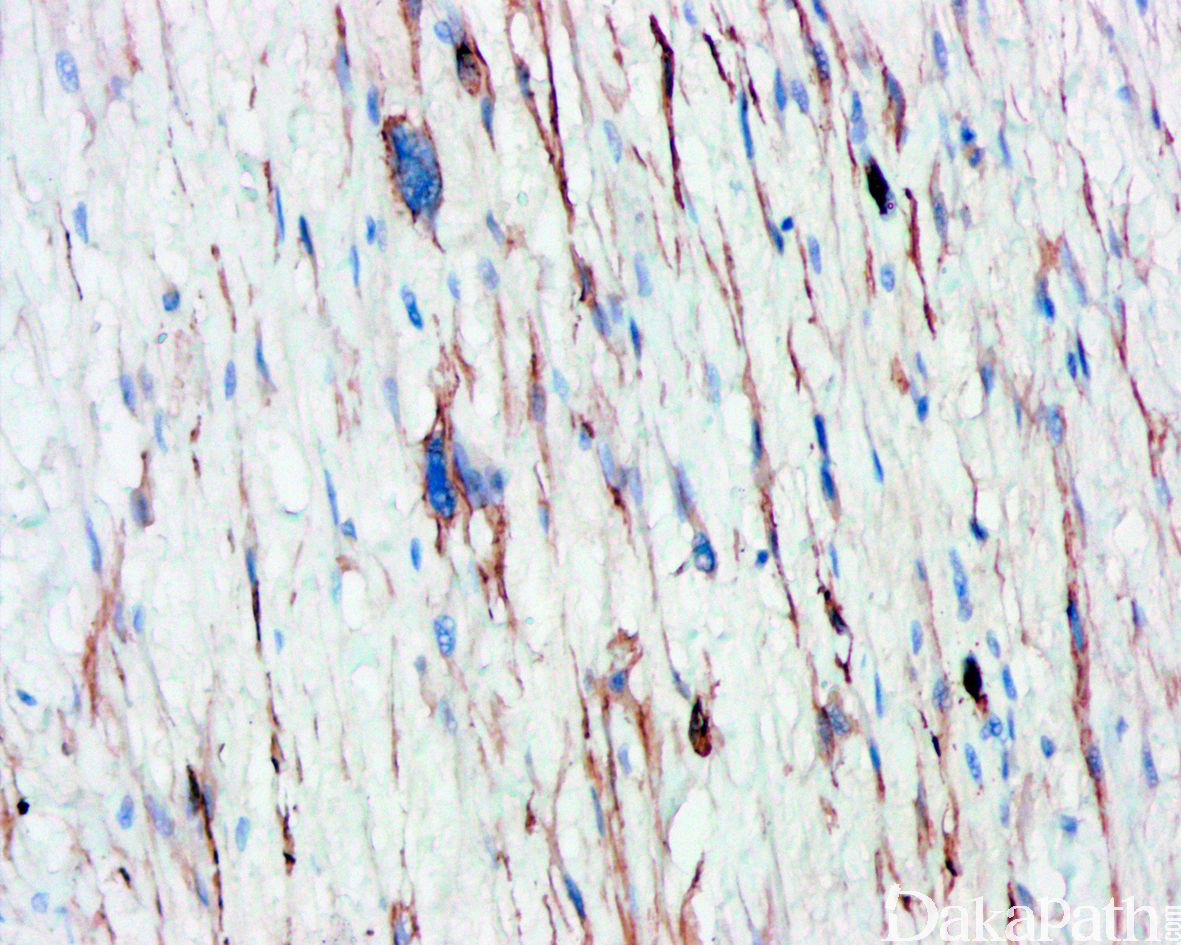

免疫组织化学染色,绝大多数的 DDLPS 弥漫强表达 p16 蛋白(核和质表达),是诊断 DDLPS 最敏感的标志物,但缺乏特异性,许多与之形态学相似的肿瘤,特别是高级别肿瘤(如平滑肌肉瘤和肉瘤样癌等)亦可弥漫表达 p16。由于 DDLPS 一致性的存在 12q14-15 区域的扩增和过表达,而 MDM2 蛋白和 CDK4 蛋白的强表达与相应的基因扩增存在高度的一致性,因此免疫组织化学染色 MDM2 和 CDK4 的共表达(均为弥漫核表达)对于诊断 DDLPS 具有较大的帮助。在与 ALT/WDLPS 之外的其他类型的脂肪源性肿瘤的鉴别诊断中,联合应用 p16. MDM2 和 CDK4 对于诊断 DDLPS 具有高度的敏感性和特异性,93%的 DDLPS 表达上述 3 个标志物中的至少 2 个,72%表达全部 3 个标志物。但在 DDLPS 与非脂肪源性的肿瘤鉴别诊断时,上述 3 个标志物的特异性则明显不够;此时,应用荧光原位杂交(FISH)检测 MDM2 基因的扩增对于诊断 DDLPS(在适当的组织学背景下)具有高度的特异性和敏感性,尤其是在小活检标本、未见典型的 ALT/WDLPS 成分、低级别去分化和少见特殊类型的 DDLPS 诊断时更是如此。MDM2 基因的扩增目前普遍认为是诊断 ALT/WDLPS 和 DDLPS 的金标准,需要指出的是,MDM2 基因扩增并非 ALT/WDLPS 和 DDLPS 所特有,其他常见存在 MDM2 基因扩增的肿瘤还包括低级别中央型骨肉瘤、骨旁骨肉瘤以及原发的心脏内膜肉瘤等。约半数左右的 DDLPS 可局灶或弥漫表达 CD34,去分化成分一般不表达 S100 蛋白,伴有肌纤维母细胞分化者可表达 SMA 和 MSA 或结蛋白[23],伴有横纹肌和平滑肌分化者可分别表达 MyoD1 和 H-caldesmon,具有脑膜上皮瘤样漩涡特征的 DDLPS 可表达 SMA 和 Claudin-1 提示其肌纤维母细胞或神经束膜分化的特征。新近发现,约 6%的 DDLPS 可见 H3k27me3 的表达缺失易与恶性外周神经鞘膜瘤(MPNST)混淆,约 11%的 DDLPS 可见 STAT6 基因扩增从而局灶或弥漫表达 STAT6 易误诊为孤立性纤维性肿瘤(SFT)。